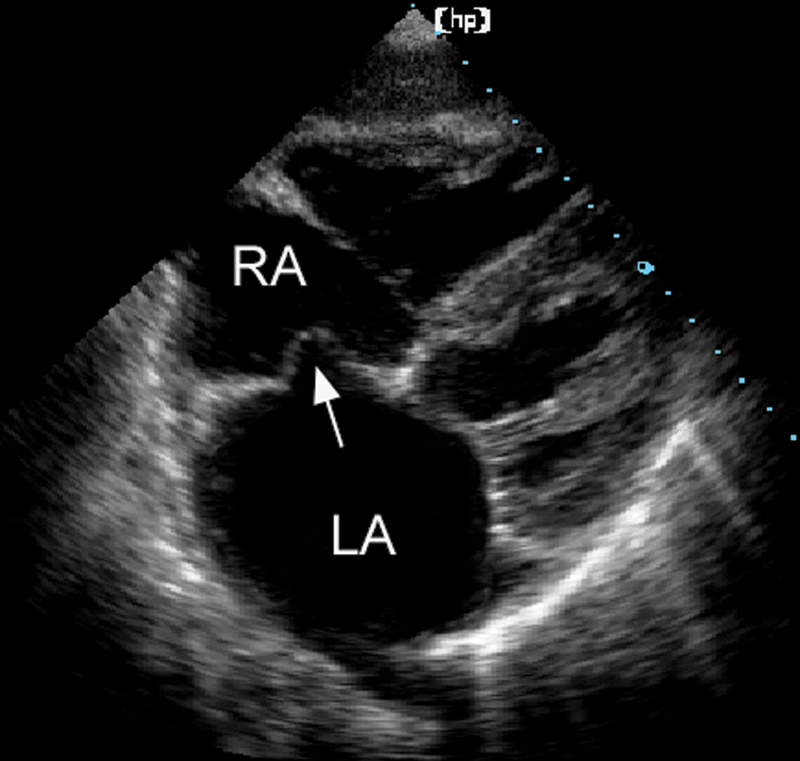

فحوصات تشخيصية لبعض امراض القلب والشرايين التاجية